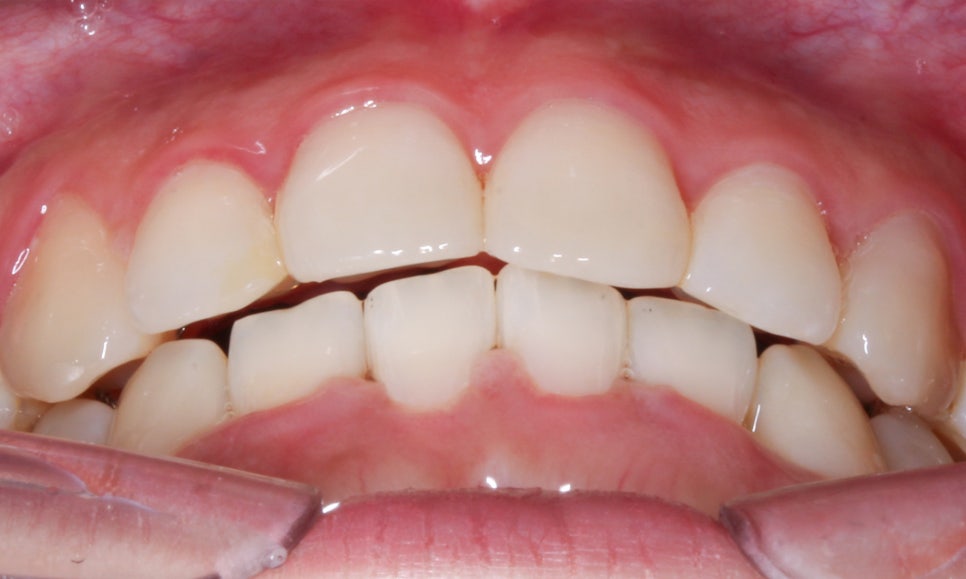

역삼역치과 덧니 case의 교정 후 overbite 사진입니다.

상악과 하악 사이가 깊게 물리는 deep bite 증상이

완화되었고 상하악의 midline도 일직선으로 바르게

교정된 모습을 확인할 수 있습니다.